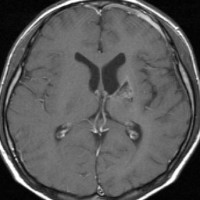

ICE化学療法投与開始から数日で小さくなります

この例は古いので第3脳室開窓術 ETV をしていません。左はICE化学療法前。中央は9日後。右は25日後です。閉塞性水頭症があっても1週間くらいで中脳水道が通って水頭症は改善します。ジャーミノーマであれば,ICE化学療法1コースでかなり縮小するはずです。このような顕著な効果がない時には,逆にジャーミノーマ以外の胚細胞腫瘍が混在していると考えた方がいいでしょう。多くは奇形腫の混在です。